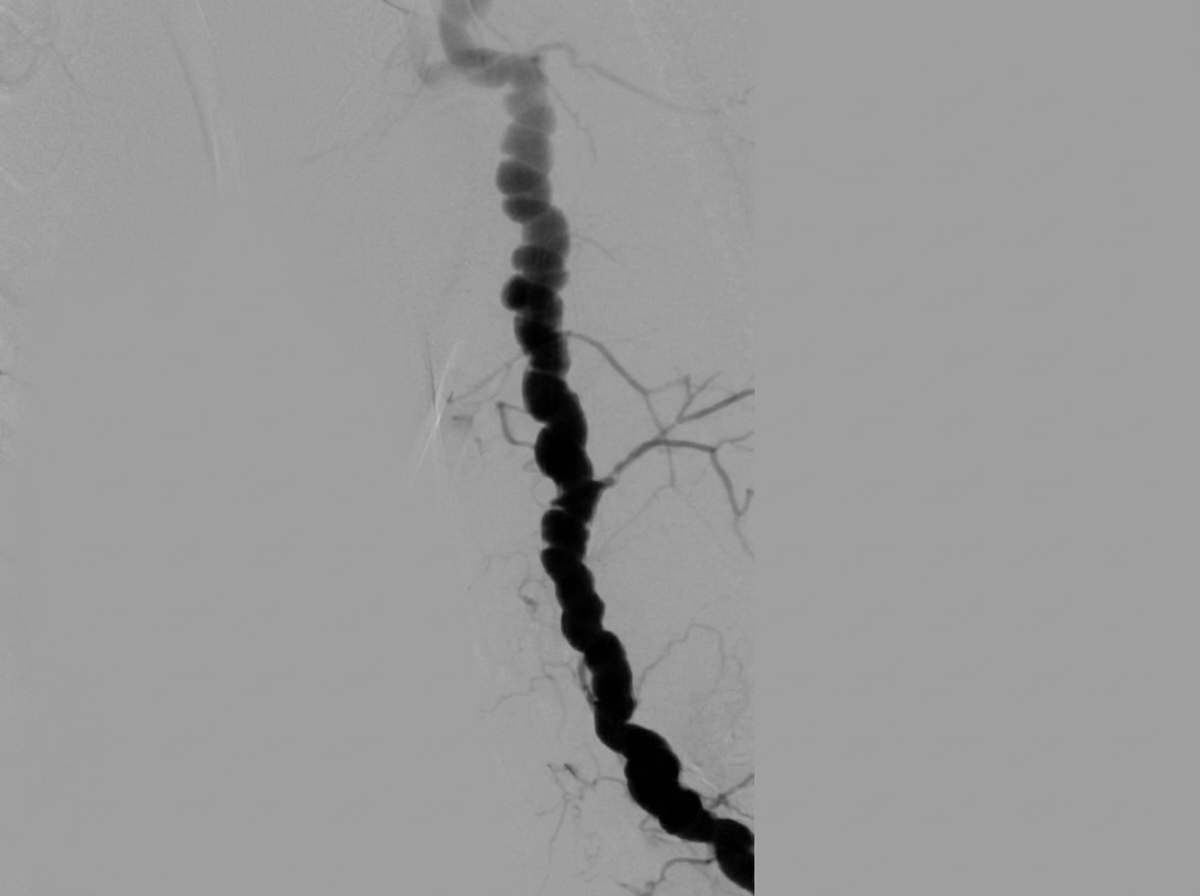

A 68-year-old woman presented with unstable angina and underwent cardiac catheterization by radial access. There was difficulty advancing the guidewire; a brachial angiogram revealed the following. What is the diagnosis?

Explanation: ***Fibromuscular dysplasia*** - The brachial angiogram likely shows the classic **"string of beads"** appearance, which is pathognomonic for **fibromuscular dysplasia** affecting the brachial artery. - **FMD** is more common in **women** and can be encountered as a complication during **transradial catheterization**, causing difficulty in guidewire advancement. *Takayasu's arteritis* - Typically affects the **aorta and its major branches** in young Asian women, not isolated brachial artery involvement. - Would show **long-segment stenosis** or occlusion rather than the beaded appearance characteristic of FMD. *Arteriovenous malformation* - Would demonstrate **early venous filling** and **arteriovenous shunting** on angiography, not stenotic segments. - Presents with **pulsatile masses**, **bruits**, or **high-output heart failure**, not guidewire advancement difficulty. *Brachial artery stenosis* - Would show **smooth, focal narrowing** without the characteristic beaded appearance seen in FMD. - Usually caused by **atherosclerosis** or **trauma**, presenting as uniform stenotic lesions rather than alternating areas of stenosis and dilatation.